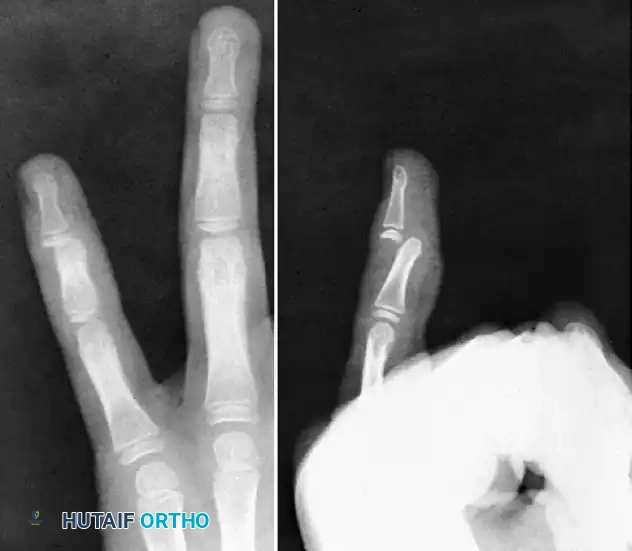

FIGURE 67-63 Undiagnosed interphalangeal dislocation in an adult complicated by an infected wound. Bone has been eroded. At 6 weeks after injury, the infection had been controlled, and the joint was arthrodesed.

When joint destruction is absolute, PIP joint arthrodesis is the salvage procedure of choice. The joint is typically fused at 40 to 50 degrees of flexion for the index and middle fingers, and 50 to 70 degrees for the ring and small fingers, utilizing crossed Kirschner wires or a tension band construct to maximize grip strength.